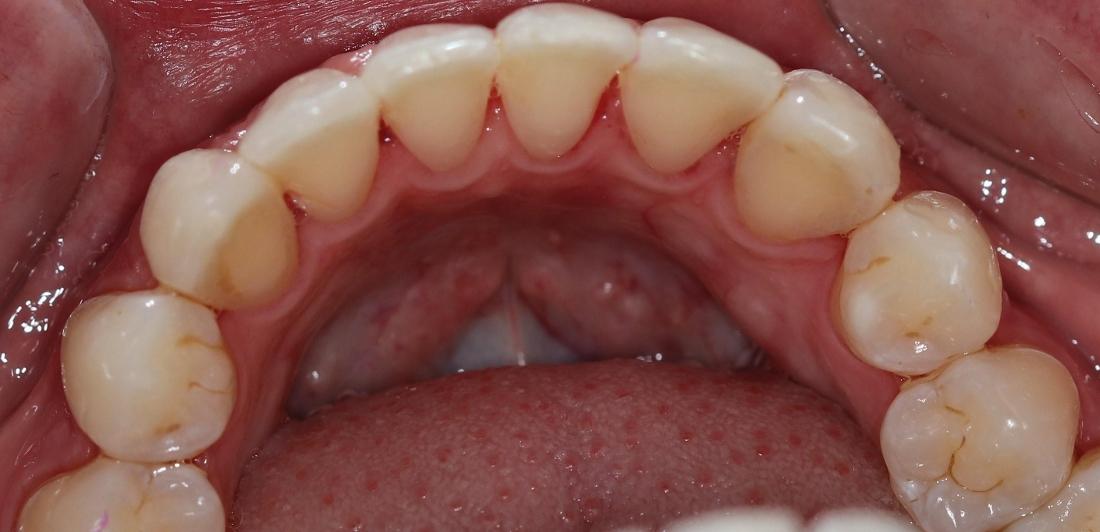

This dental patient arrived at our dental office in Goffstown requesting a straighter smile. We knew this patient would be a perfect candidate for Invisalign clear aligner treatment. After a short consultation, our expert dental team got to work on the Invisalign process and in a few short months, this patient was able to smile with confidence.

One of the first priorities was getting my teeth straightened. I was surprised when I was offered a solution right there at my primary dentist office and did not have to travel to a specialist. I recently got my brackets removed after about a year and the results are AMAZING! The best part was the level of care I received along the way. Any time I had a question or concern it was addressed immediately and they always made time for me to stop by. They have been exceptional with the level of patient care they provide!